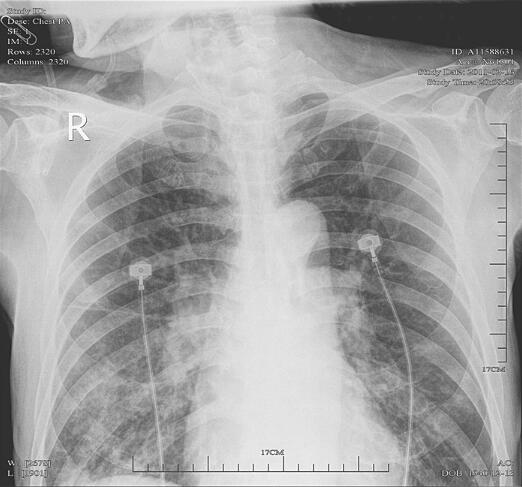

辅助检查:急诊血常规:白细胞18.8×109/L,中性粒细胞87.5%,中性粒细胞16.50×109/L,血红蛋白121.0g/L,血细胞比容33.9%,血小板216×109/L;血生化:尿素氮7.59mmol/L,肌酐114.4μmol/L,尿酸381μmol/L,谷草转氨酶28U/L,乳酸脱氢酶120U/L,磷酸肌酸激酶102U/L,肌酸激酶同工酶3U/L,钠离子137.4mmol/L,钾离子3.63mmol/L,氯离子96.0mmol/L,钙离子2.07mmol/L,超敏CRP 90.00mg/L;血BNP 720pg/ml;血TnI(−);动脉血气分析:pH 7.440,二氧化碳分压39.0mmHg,氧分压84.0mmHg,碳酸氢根浓度26.0mmol/L,标准碳酸氢根26.00mmol/L,剩余碱2.0mmol/L,氧饱和度96.0%;心电图:快速性房颤,左胸导联ST段压低,T波低平、浅倒;心脏超声:EF 42.3%,FS 30.3%,左心房增大,肺动脉收缩压轻度增高;胸片:两肺散在斑片状影(图1)。

图1 胸片:两肺散在斑片状影